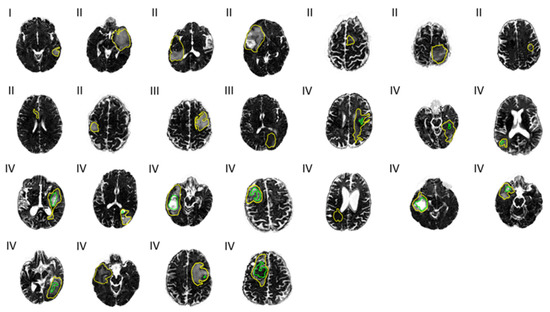

There is a larger variance in the distribution of the mean FW in the necrotic tumor region than in other parts of the tumor (Figure 2), and the mean FW is significantly higher in the necrotic region (FWmean = 0.50) than in both the enhancing (FWmean = 0.30) and non-enhancing (FWmean = 0.30) regions in grade IV patients (p ≤ 0.015), as well as in the total tumor volume region across all patients (FWmean = 0.33). Mean FAt is significantly lower (p ≤ 0.001) in the necrotic tumor region (FAtmean = 0.13) than in the other defined tumor regions (FWmean ≤ 0.27). Measurements of FA and FW from the enhancing, non-enhancing, and total tumor regions do not differ statistically significantly from one another. Although there may be tendencies toward higher MD in the necrotic region compared to non-necrotic regions, conventional MD that is not corrected for FW does not significantly differentiate between tumor regions (Supplementary Material, Figure S1).

FW maps with cross-sections of total and necrotic tumor regions overlaid can be seen in Figure 3. The variance in mean FW, as mentioned above, may be visually suggested by the varying gray scale levels representing high and low FW content within the necrotic areas (green outline).

Figure 3. Free water (FW) maps across 25 patients. Tumor grades I, II, III, and IV are noted to the top left at each map. Outlines of the total tumor regions (yellow) and necrotic tumor regions (green) are overlaid.